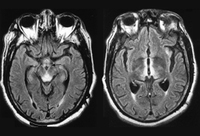

Wernicke's encephalopathy

Fluid attenuated inversion recovery (FLAIR) MRI brain of patient with Wernicke's encephalopathy

Ramulu P, Moghekar A, Chaudhry V, et al. Wernicke's encephalopathy, Neurology 2002;59:846; used with permission